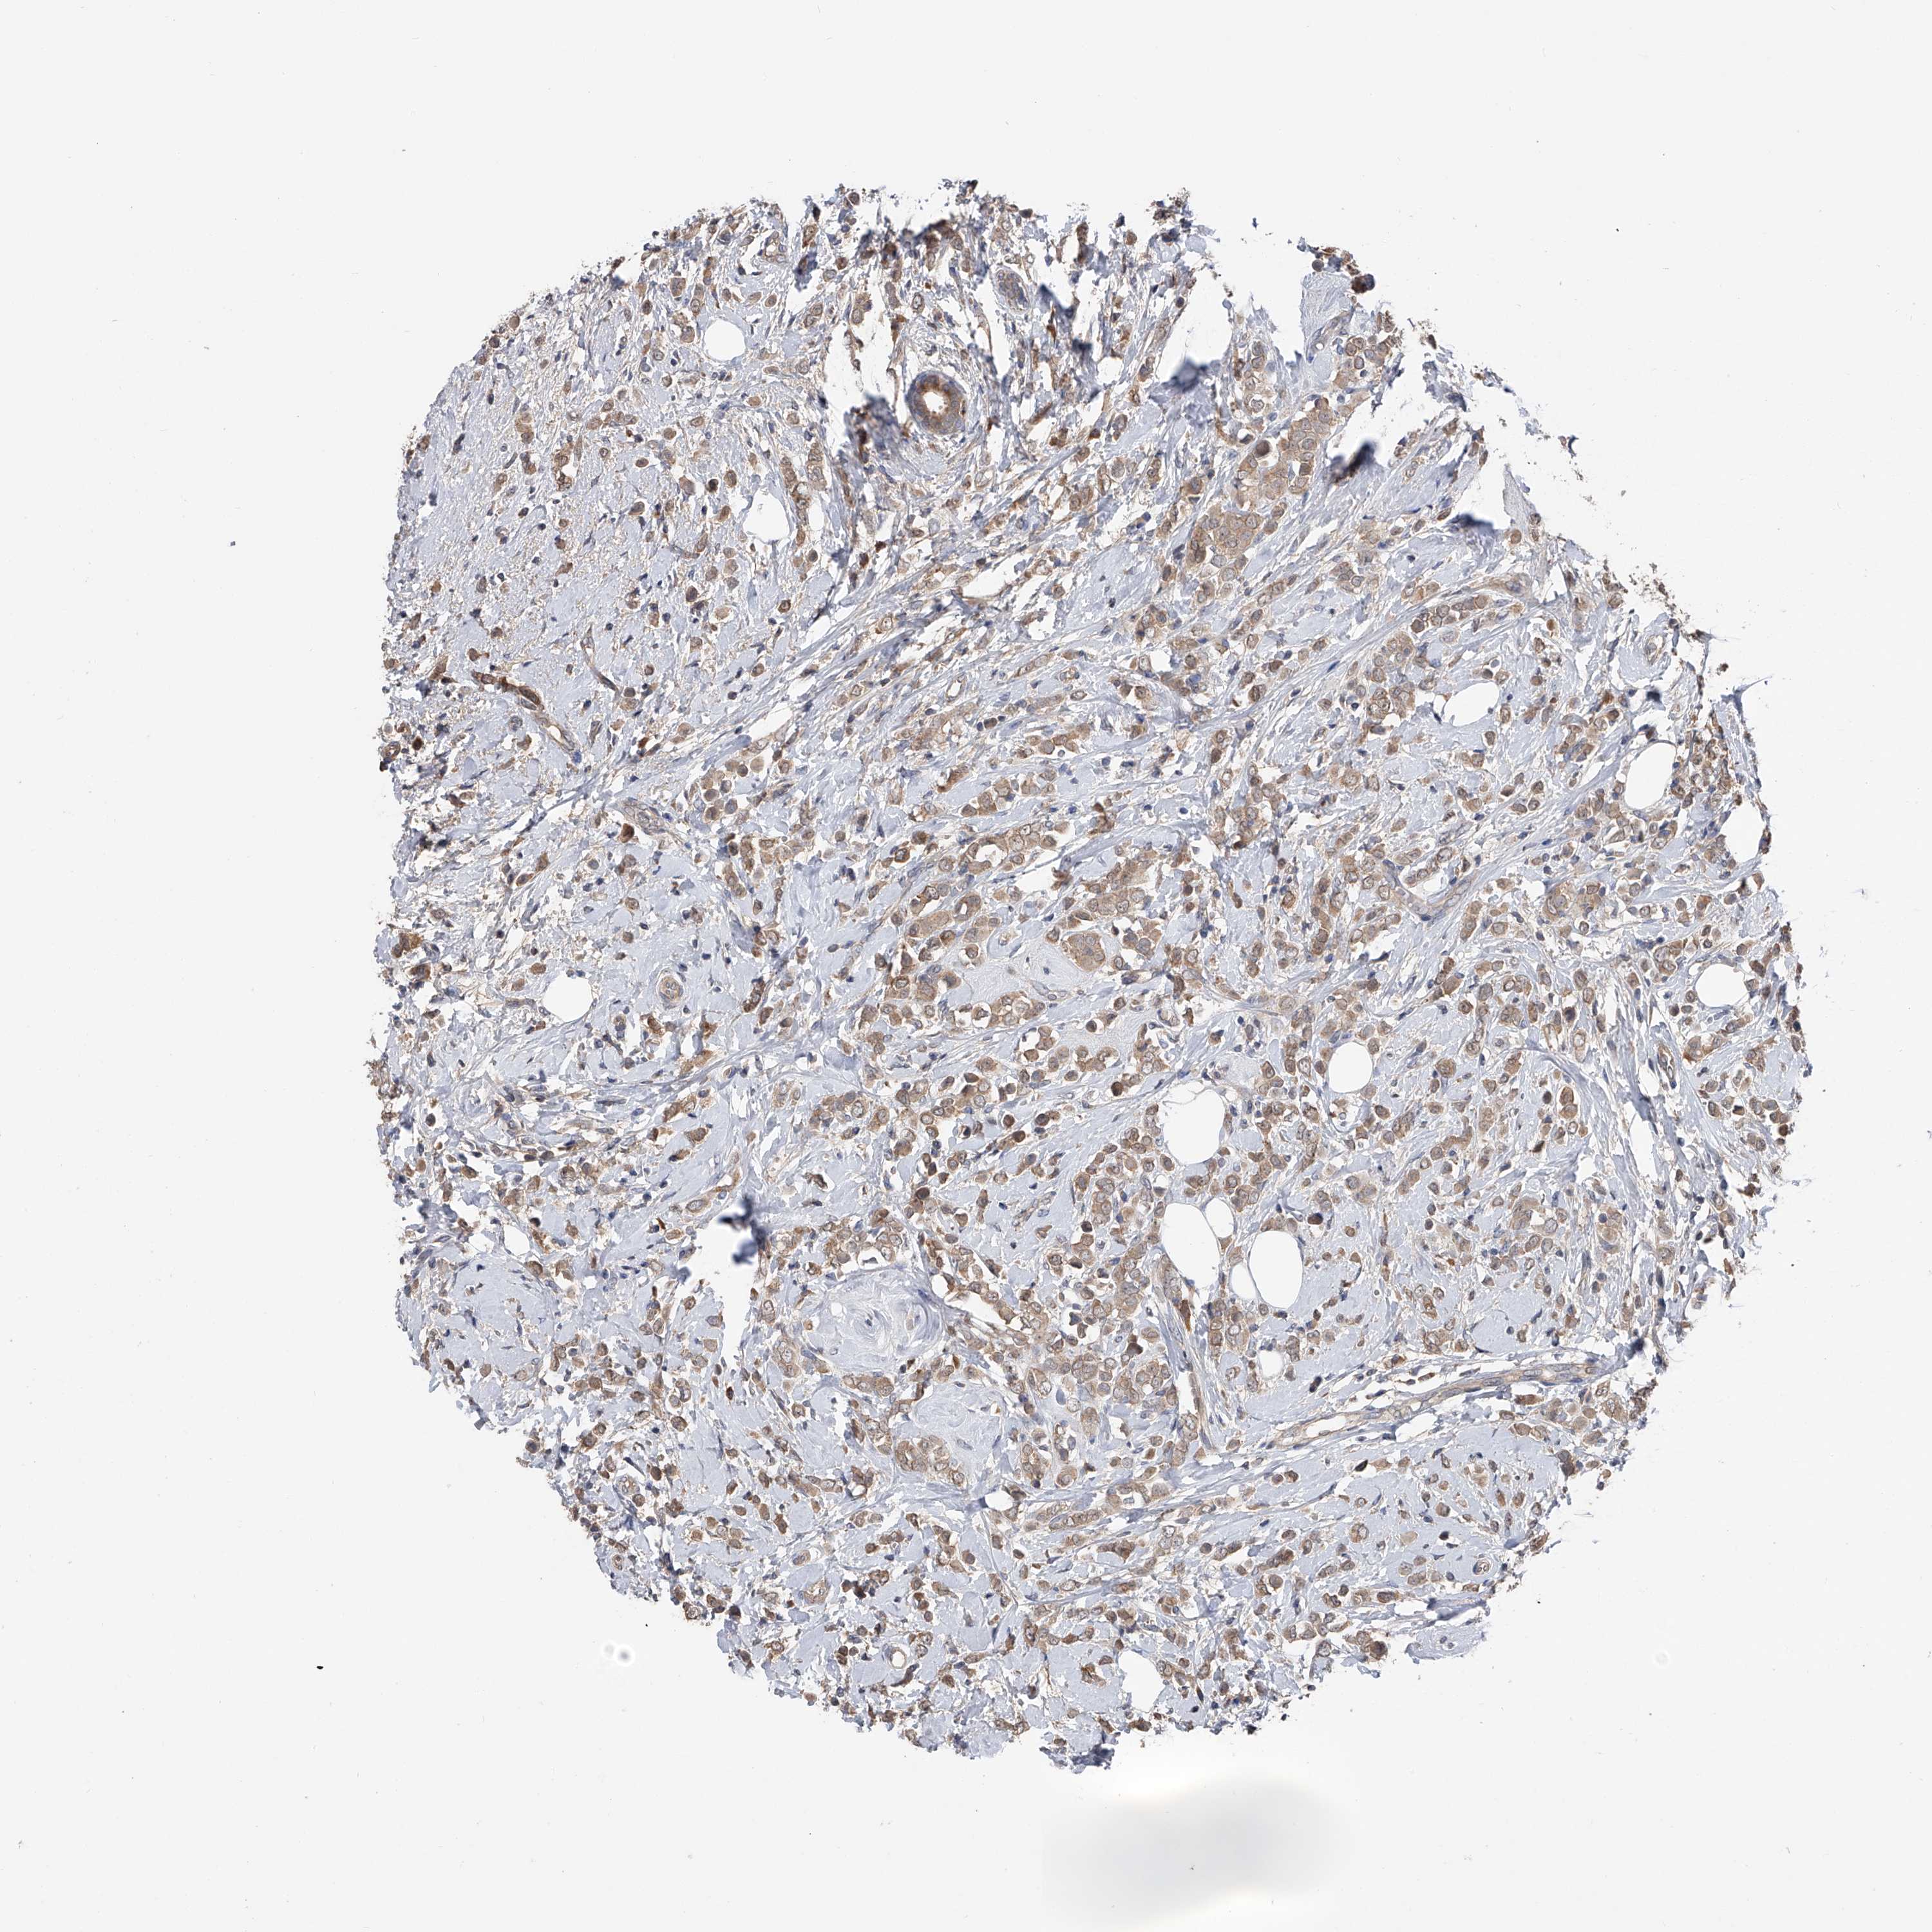

CANCER BREAST CANCER Show tissue menu

BRCA TCGA BRCA VALIDATION PROTEIN EXPRESSION